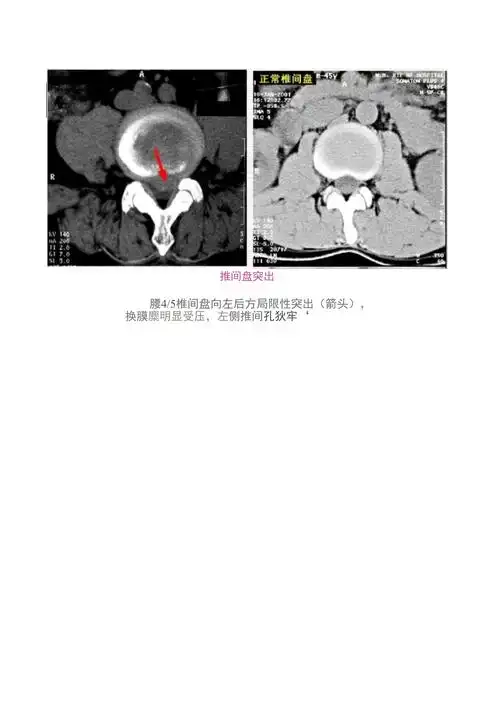

腰椎ct扫描层面及常见疾病的诊断附真实病例